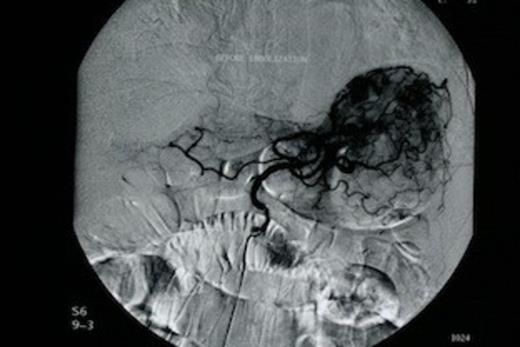

The patient was subjected to emergency oesophago-gastroduodenoscopy, which revealed extensive angiodysplasia of the gastric body. At first, conservative management was attempted with intravenous fluids and transfusions. After initial stabilization of the patient (Ht: 32.5%, 90bpm, 110/50mmHg), rebleeding was encountered within 48 hours and therefore decision for interventional radiology, embolization of the angiodysplasia, was made. Urgent angiography of the left gastric artery revealed extravasation of contrast material from the gastric body (Figure 1). Following that, successful arterial coil embolization, using super selective catheterization was achieved in the distal and proximal parts of the ruptured vessel (Figure 2). Consequently the patient recovered from the hemorrhagic shock.

Urgent angiography of the left gastric artery revealed extravasation of contrast material from the gastric body